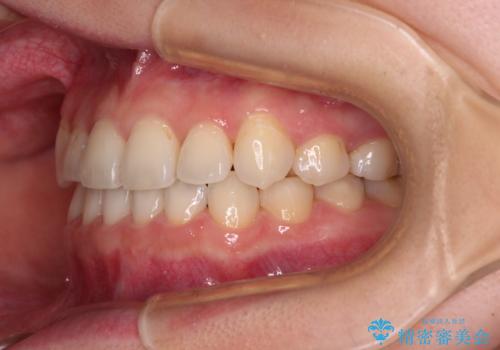

- 八重歯を気にして来院された患者様です。

口腔内の状況を確認したところ、左右ともに下顎第二大臼歯が欠損しており、咬み合うべき上顎の第二大臼歯が著しく挺出していました。

挺出した大臼歯を元の位置に戻すことは現実的に難しいため抜歯することとし、補助装置とワイヤー装置により上顎歯列全体を後方に移動することとしました。